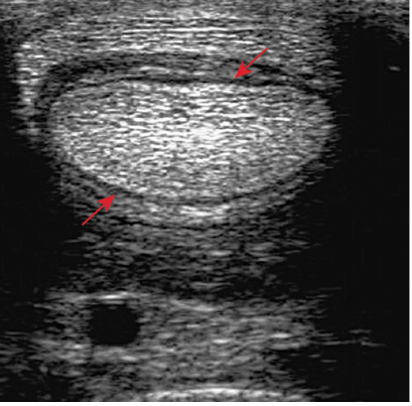

- The sheath is distended by anechoeic fluid. The arrows show the swollen synovial tissue, which is separating the DDFT from the SDFT and its manica flexoria.